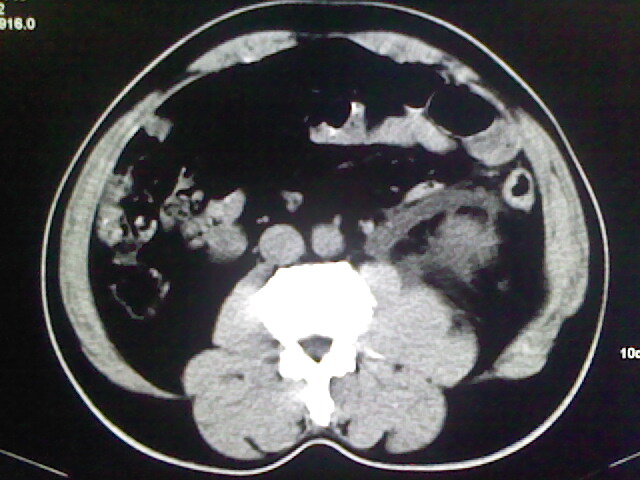

以下是引用zsl6918在2009-2-7 7:29:00的发言:[br]请提供介入的方式方法,肾及输尿管改变考虑与介入损伤有关,漏了,尿液外渗。

以下是引用余辉在2009-2-7 8:27:00的发言:[br]可能是硬化剂烧穿囊壁进入肾盂输尿管了,尿漏。不除外介入或碎石术后合并感染[br]患者术后怀疑结石,接着就碎石了?就怀疑没有确诊吗?碎石用的什么方法?气压弹道还是体外超声?如果这样的话责任人都难找

以下是引用随光逐影在2009-2-7 8:46:00的发言:[br]支持3楼意见。[br]另:不排除左肾及肾周感染可能。